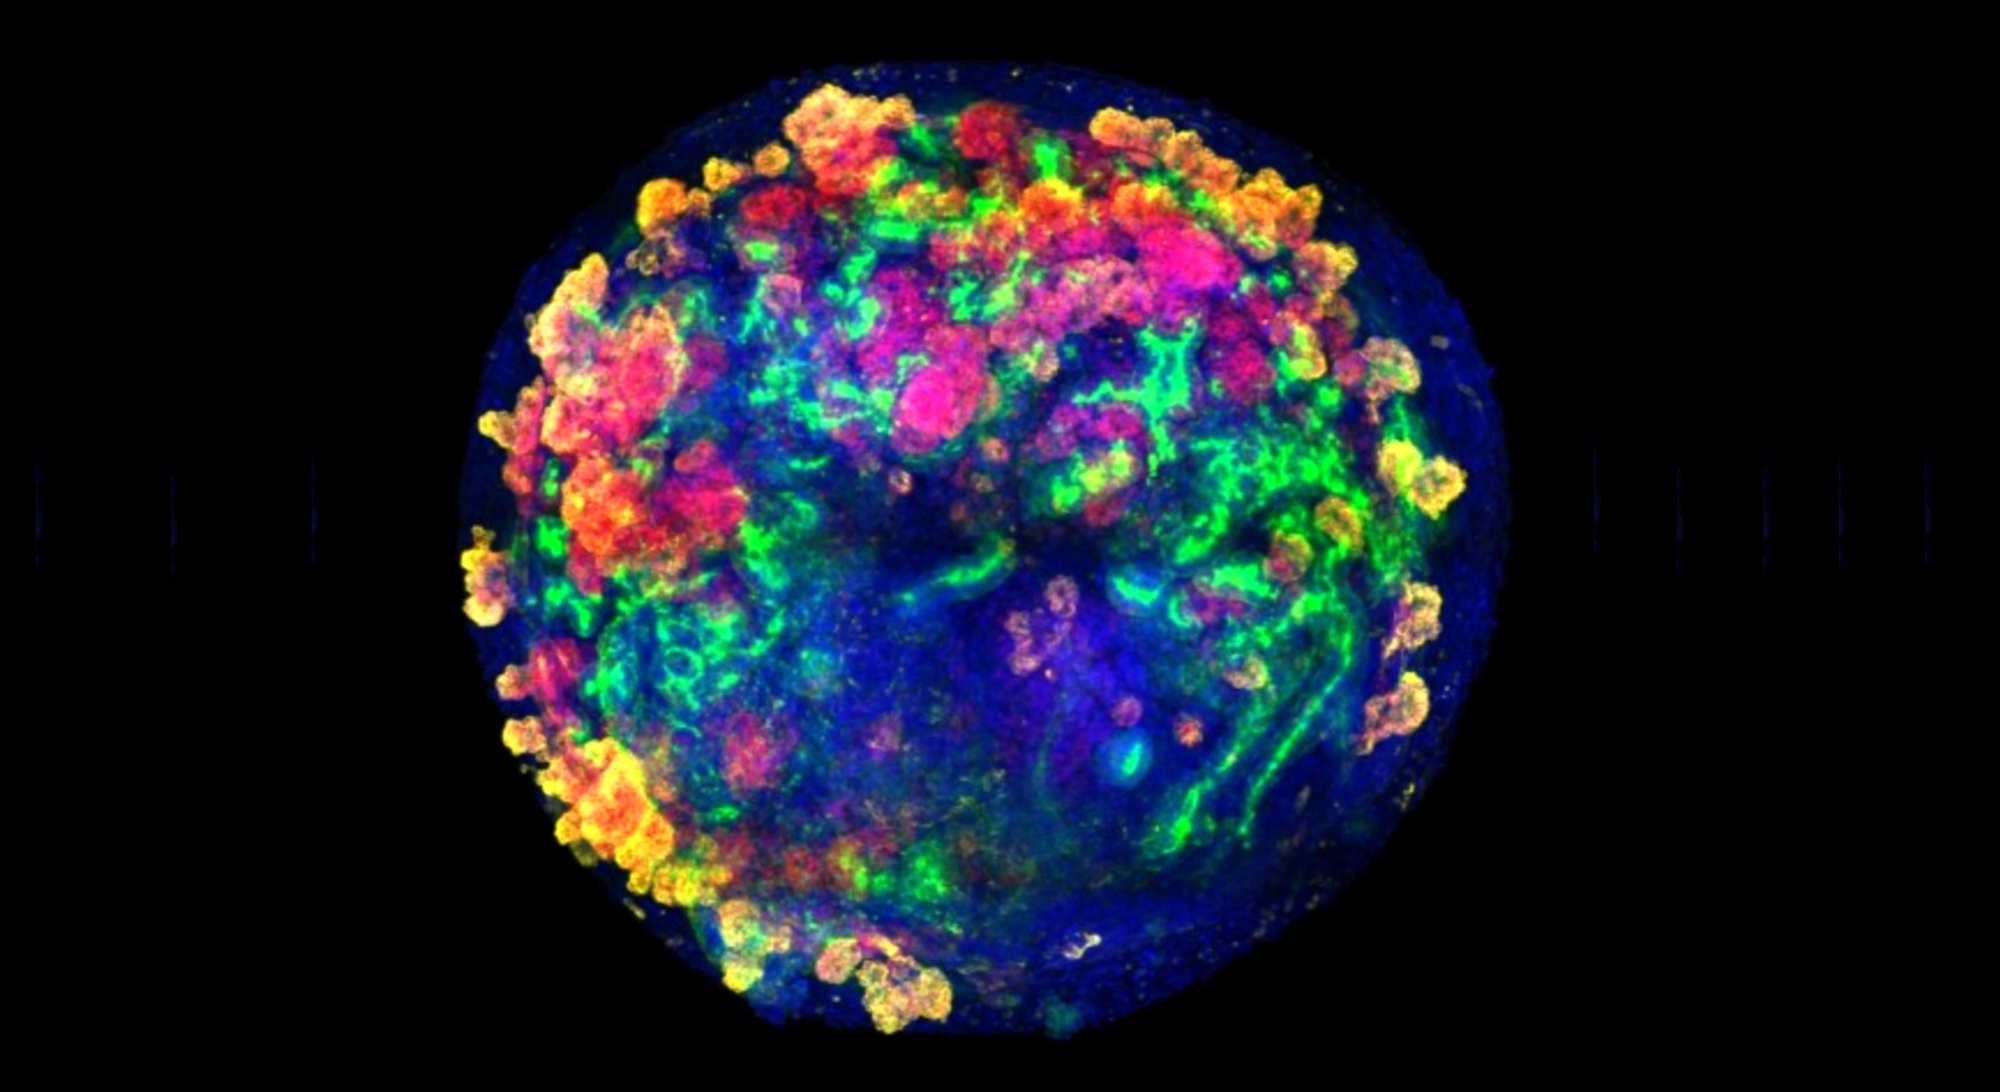

Un organoide de riñón es una estructura tridimensional, de unas micras de tamaño, cultivada en el laboratorio a partir de células madre humanas. Aunque no es un órgano completo, reproduce muchas de sus estructuras y funciones principales. Gracias a estas características, los organoides permiten estudiar cómo se desarrolla el riñón, probar nuevos fármacos y, en el futuro, se espera que puedan ser utilizados para reparar tejidos renales dañados o mejorar órganos destinados al trasplante. El estudio describe, por primera vez, un método sistemático y escalable de ingeniería genética para producir miles de estos organoides renales humanos.

Los resultados son fruto del trabajo de más de una década dedicada a estudios de medicina regenerativa y bioingeniería de órganos. El equipo de investigación ha conseguido combinar por primera vez organoides renales humanos con riñones porcinos vivos, conectados a máquinas de perfusión normotérmica. El uso de estos dispositivos, utilizados habitualmente en el quirófano para mantener el órgano vivo y oxigenado fuera del cuerpo antes de un transplante, ha permitido insertar organoides humanos dentro de los riñones porcinos y evaluar en tiempo real su integración y función.

La utilización de las máquinas mencionadas, para llevar a cabo la perfusión de los organoides dentro de los riñones, ofrece una ventaja clave: permite medir parámetros fisiológicos del órgano en tiempo real y detectar de manera inmediata cualquier signo de daño o rechazo. Los experimentos se realizaron tanto ex vivo (fuera del organismo) como in vivo (en el mismo animal), utilizando un modelo porcino de trasplante muy similar al riñón humano.

El equipo de investigación observó que, después de 24 y 48 horas del trasplante, los organoides humanos persistían integrados en el tejido renal porcino, mantenían su viabilidad y no desencadenaban ninguna respuesta inmune significativa. El riñón trasplantado continuaba funcionando con normalidad, y no se detectaron signos de daño ni toxicidad.